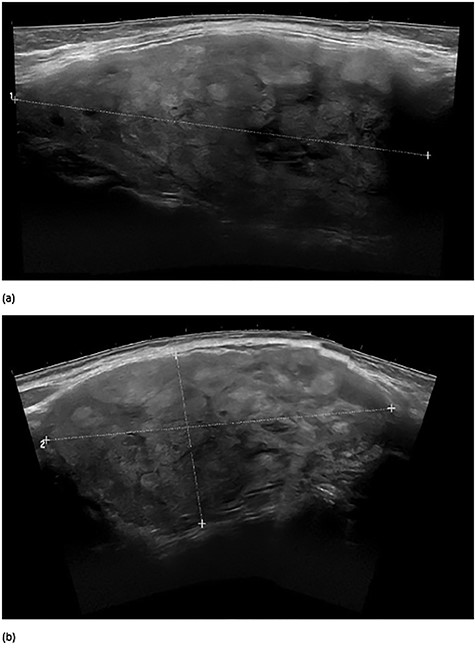

A 48-year-old morbidly obese woman with a history of metastatic endometrial carcinoma who was status post-total abdominal hysterectomy and bilateral salpingo-oophorectomy presented for evaluation of a large right-sided goiter found incidentally on computed tomography (CT) performed as part of her metastatic cancer evaluation. CT revealed a 10 cm right thyroid mass with extension deep to the right clavicle and associated tracheal compression (Fig. 1). Positron emission tomography revealed no evidence of metastatic disease but displayed diffuse thyroid hypermetabolism.

Preoperative computed tomography images highlighting large right thyroid nodule with tracheal compression.